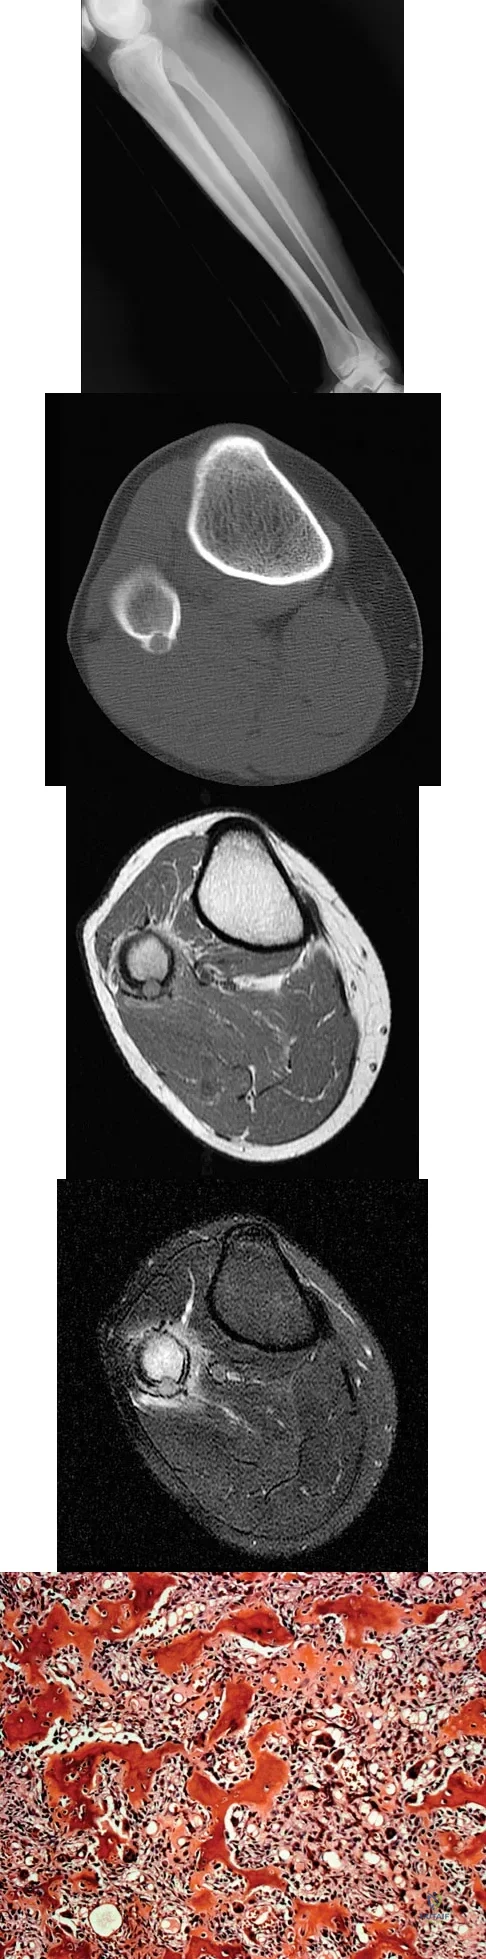

A 14-year-old patient has anterior knee pain. Radiographs, an MRI scan, and biopsy specimens are shown in Figures 6a through 6e. What is the most likely diagnosis?

Options:

- Unicameral bone cyst

- Aneurysmal bone cyst

- Giant cell tumor

- Chondromalacia

- Ewing's sarcoma

Correct Answer: Ewing's sarcoma

Explanation:

Although the imaging studies are consistent with a unicameral bone cyst, aneurysmal bone cyst, or giant cell tumor, the histology shows small round blue cells that are typical of Ewing's sarcoma. Although Ewing's sarcoma frequently occurs in the diaphysis, it can occur in the metaphysis.

References:

Mirra J: Bone Tumors: Clinical, Radiologic, and Pathologic Correlations. Philadelphia, PA, Lea & Febiger, 1989, vol 2, ch 18.